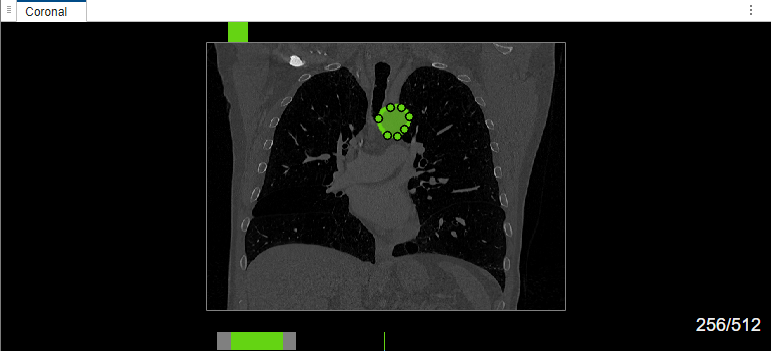

Select label Type2. Draw a bounding box around the object to segment in the coronal plane of the volume. The MedSAM algorithm extracts the embeddings of the image and segments the object in the bounding box. Right-click the labeled object, and, from the context menu, select Select Drawn Region. You can now edit the label shape using the points, or reassign or delete the label by using the options in the context menu.